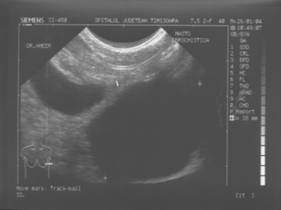

Fibroadenomul este tumora benigna cel mai frecvent asociata cu calcificari. Definitia lor histologica, corespunde unei proliferari fibro-epiteliale benigne. Exista tipuri pericanaliculare, intracanaliculare si forme mixte.

TUMORI BENIGNE

Tumorile si pseudotumorile sanului sunt patologii frecvente, dominate mai ales de fibroadenom, care este o patologie obisnuita la femeie tanara.